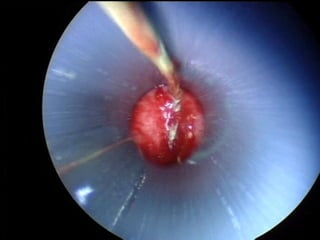

O documento discute o tratamento de urolitíase, especificamente a remoção de cálculos renais através de nefrolitotripsia. A cirurgia aberta é agora muito restrita devido aos avanços da ESWL e procedimentos endourológicos menos invasivos como ureteroscopia e cirurgia percutânea. A cirurgia laparoscópica está substituindo a cirurgia aberta como técnica menos invasiva que combina a tecnologia endourológica com a laparoscópica preservando